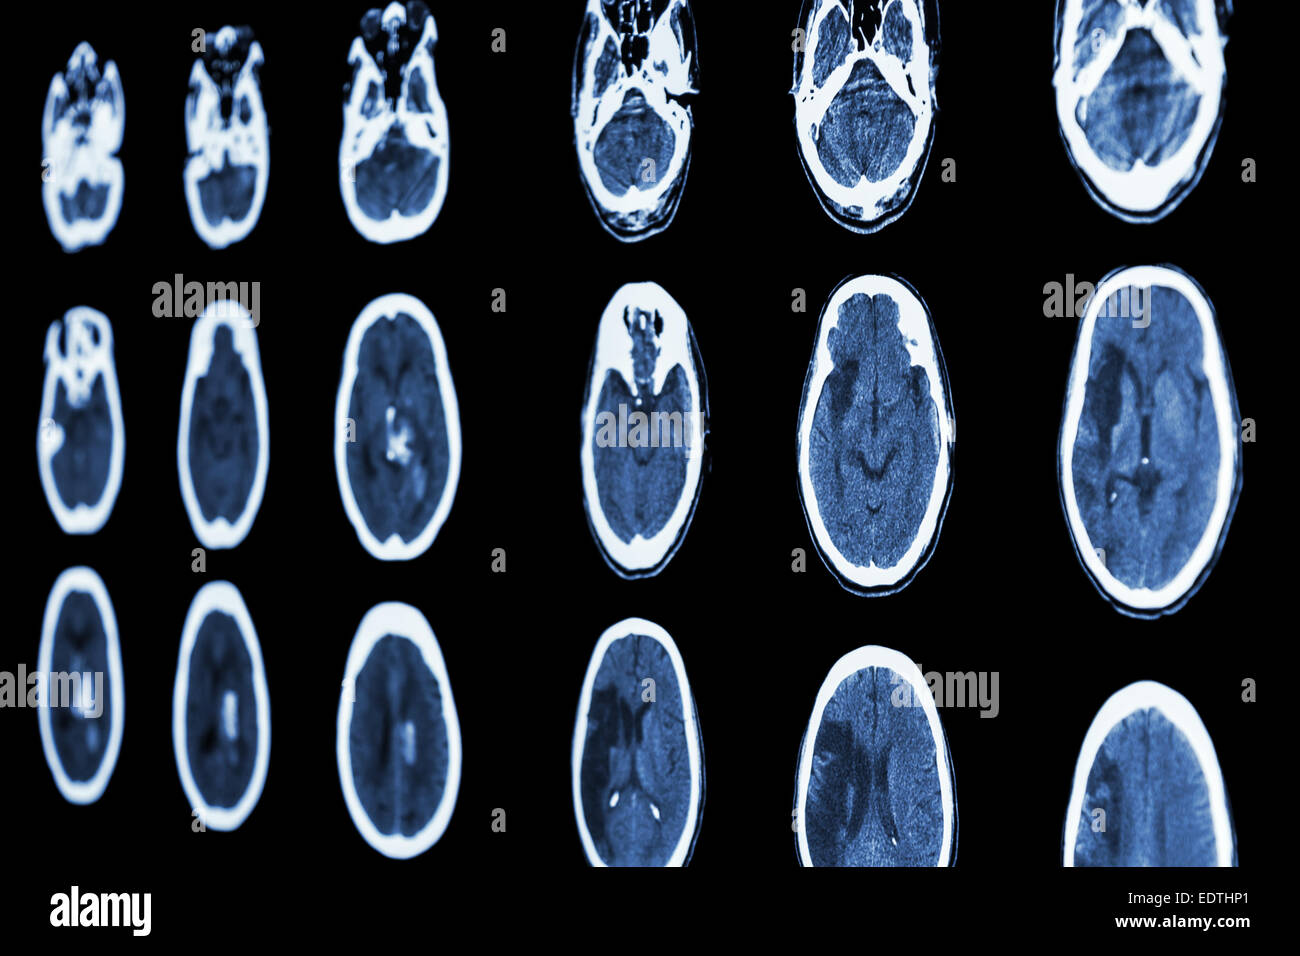

From www.alamy.com

CT scan tomography) of brain show cerebral infarction at Does A Brain Scan Show Stroke If a blocked artery (ischaemic. A brain mri (magnetic resonance imaging) scan, also called a head mri, is a painless procedure that produces very clear images of the structures inside of your head. You might have a ct (computerised tomography) scan or an mri (magnetic resonance imaging) scan. If a doctor thinks you've had a stroke, they'll do tests such. Does A Brain Scan Show Stroke.